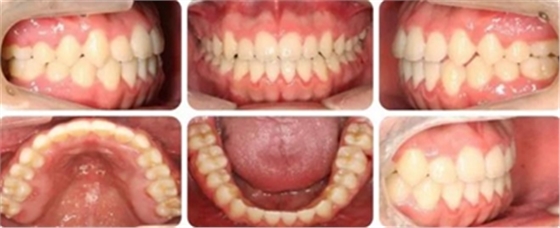

結(jié)束時(shí),可見前牙覆合覆蓋正常,上下牙列排齊,雙側(cè)尖磨牙達(dá)到中性關(guān)系。

高角反頜伴開頜病例,多采用正畸正頜聯(lián)合治療。但該患者為直面型,下牙列輕度擁擠,下前牙直立,且年齡較小,手術(shù)治療非首選。采用種植釘內(nèi)收下前牙代償性治療前牙反合。而且需要拔除阻生智齒減小遠(yuǎn)移下牙列的阻力。